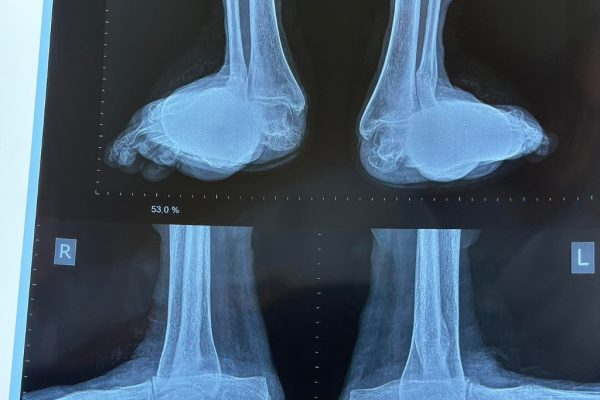

Last year we straightened up the right foot of a patient with severe deformities due to rheumatoid arthritis. Last week we gave her a matching pair. We were all delighted with the results!